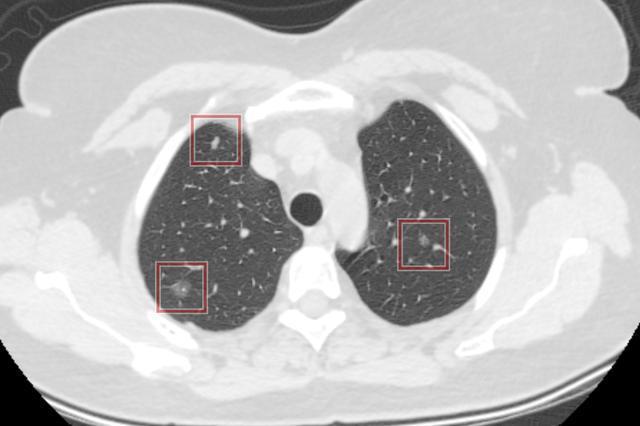

混合磨玻璃结节

多发的磨玻璃结节,慎重手术,因为病灶生长缓慢,我们不知道未来哪个结节先生长到威胁我们健康的时候,所以建议到了微浸润及以上,再根据病灶的生长位置,再决定如何手术,一次性手术切除几个病灶等,由胸外科和影像科共同做出规划。

不同阶段的多源发磨玻璃状肺腺癌